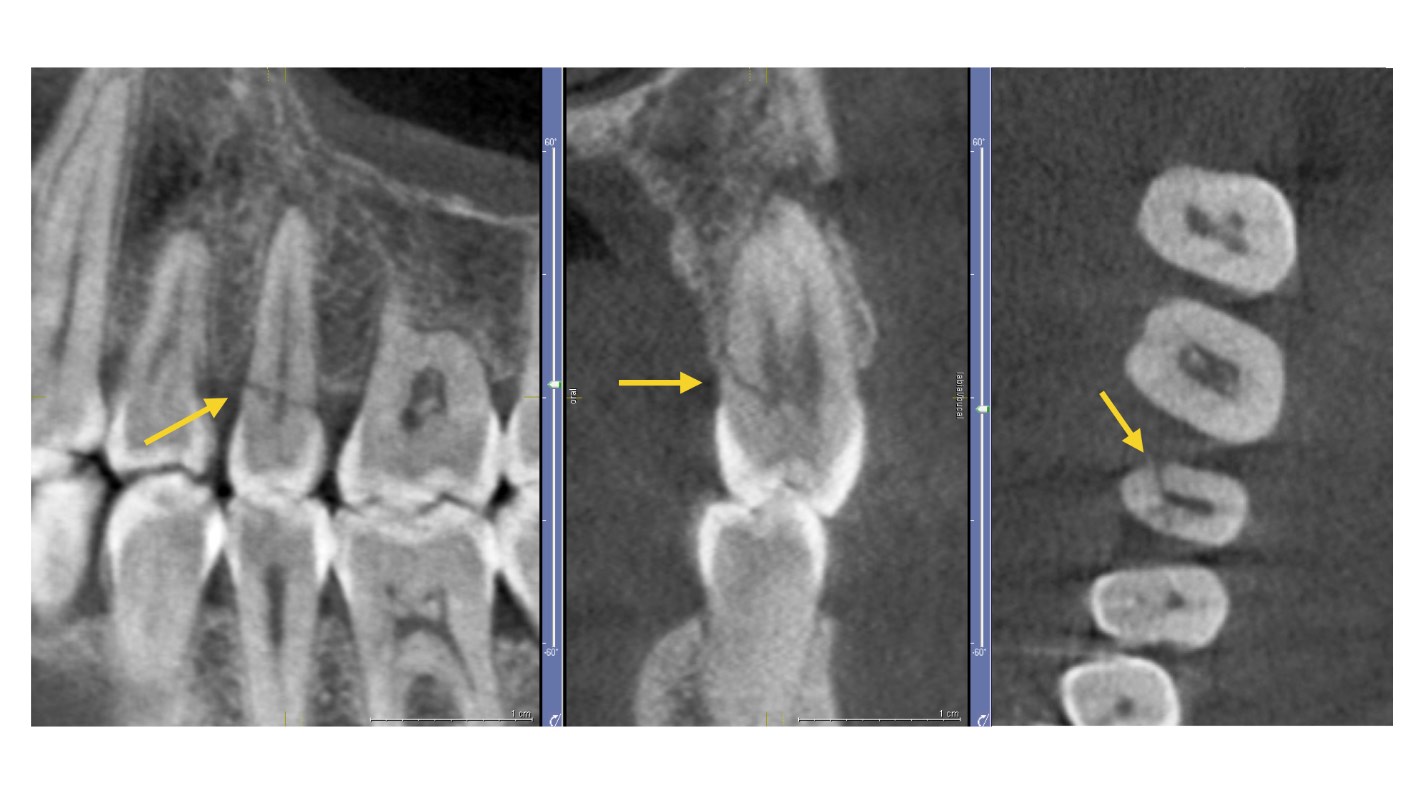

Si votre domaine de travail est l'endodontie, un scanner CBCT peut fournir une vue axiale, coronale et sagittale que vous ne pouvez pas obtenir avec la radiologie conventionnelle, bien qu'elle soit certainement plus pratique et adaptée aux procédures endodontiques les plus courantes. Le CBCT présente un grand avantage pour éliminer ou réduire le chevauchement des structures, comme par exemple pour la :

Visualisation de l'anatomie des canaux radiculaires : si vous utilisez un scanner CBCT avec un FOV limité, vous pourrez reconnaître les canaux radiculaires avec plus de précision et fournir des mesures plus précises des angulations radiculaires.

Identification de la pathologie périapicale : avec un équipement CBCT, vous aurez une plus grande sensibilité pour établir le diagnostic des lésions périapicales expérimentales. Cependant, il ne faut pas oublier les artéfacts du matériau de restauration qui pourraient entraver le diagnostic.

Identification des fractures de dents : le scanner CBCT surpasse la radiologie conventionnelle dans le diagnostic des fractures dentaires. En effet, à moins d'orienter le faisceau de manière à ce qu'il passe par le plan de la fracture, il n'est pas possible de séparer les fragments dans l'image d'une radiographie intra-orale. Ce diagnostic CBCT peut aussi être altéré par des artefacts.

Analyse du processus de résorption radiculaire interne et externe : avec votre scanner CBCT, vous pouvez non seulement détecter l'emplacement exact, mais aussi déterminer l'étendue de la résorption et la communication avec l'espace du ligament parodontal.